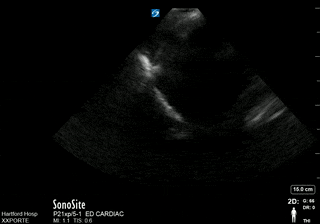

Hemothorax

| current | 13:59, 18 July 2016 | 320 × 224 (557 KB) | Neil.m.young (talk | contribs) | Hemothorax |